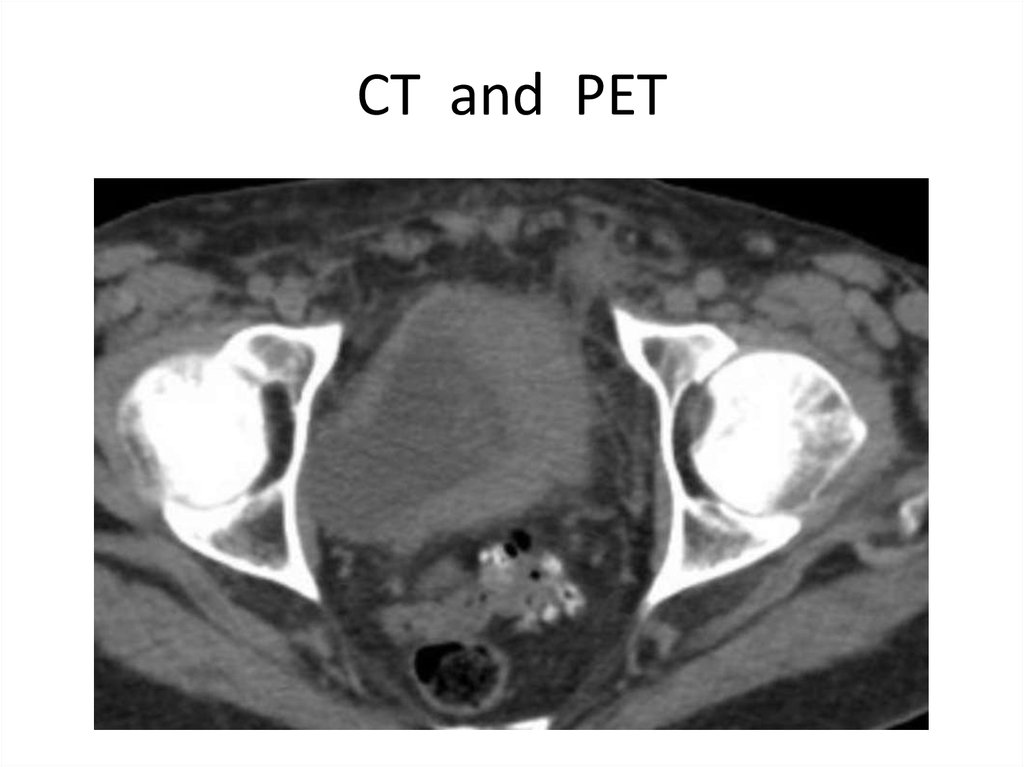

41. СT and PET